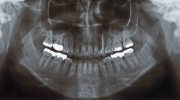

マルチブラケット終了時

治療後5年経過時